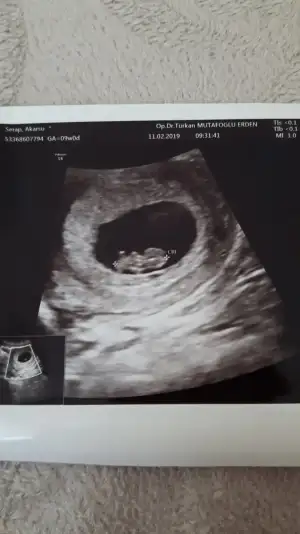

Kizlar bende tahmin istiyorum 6 haftalik yanliz kesemin hepsi gorunmuyo ama uzun bunun biyarisi daha var yani resmi yarida kesmis doktor 20190209_181812.webp

Canim soyle 5 haftalikken baktim saga yakin kese henuz boşken buhafta bebek gorundu kese saga yakin bebekse tam solda duruyo ucta resimdeki gibi